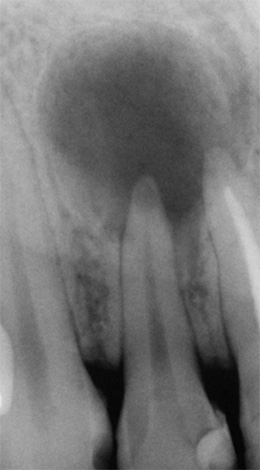

No contexto da exacerbação da periodontite, a situação com o dente é realmente deprimente:

- na cavidade cariosa, há tecidos cariados amolecidos e pigmentados;

- dentro dos canais radiculares, uma polpa inflamada ("nervo") se rompe (na verdade apodrece);

- ao redor da parte superior das raízes do dente, há graus variados de rarefação pronunciada do tecido ósseo - na imagem, ele aparece como manchas escuras, linhas, dentes, etc.

Em tal situação, existe um alto risco de deixar o processo infeccioso no buraco, mesmo depois que todas as raízes com cistos são extraídas dele.